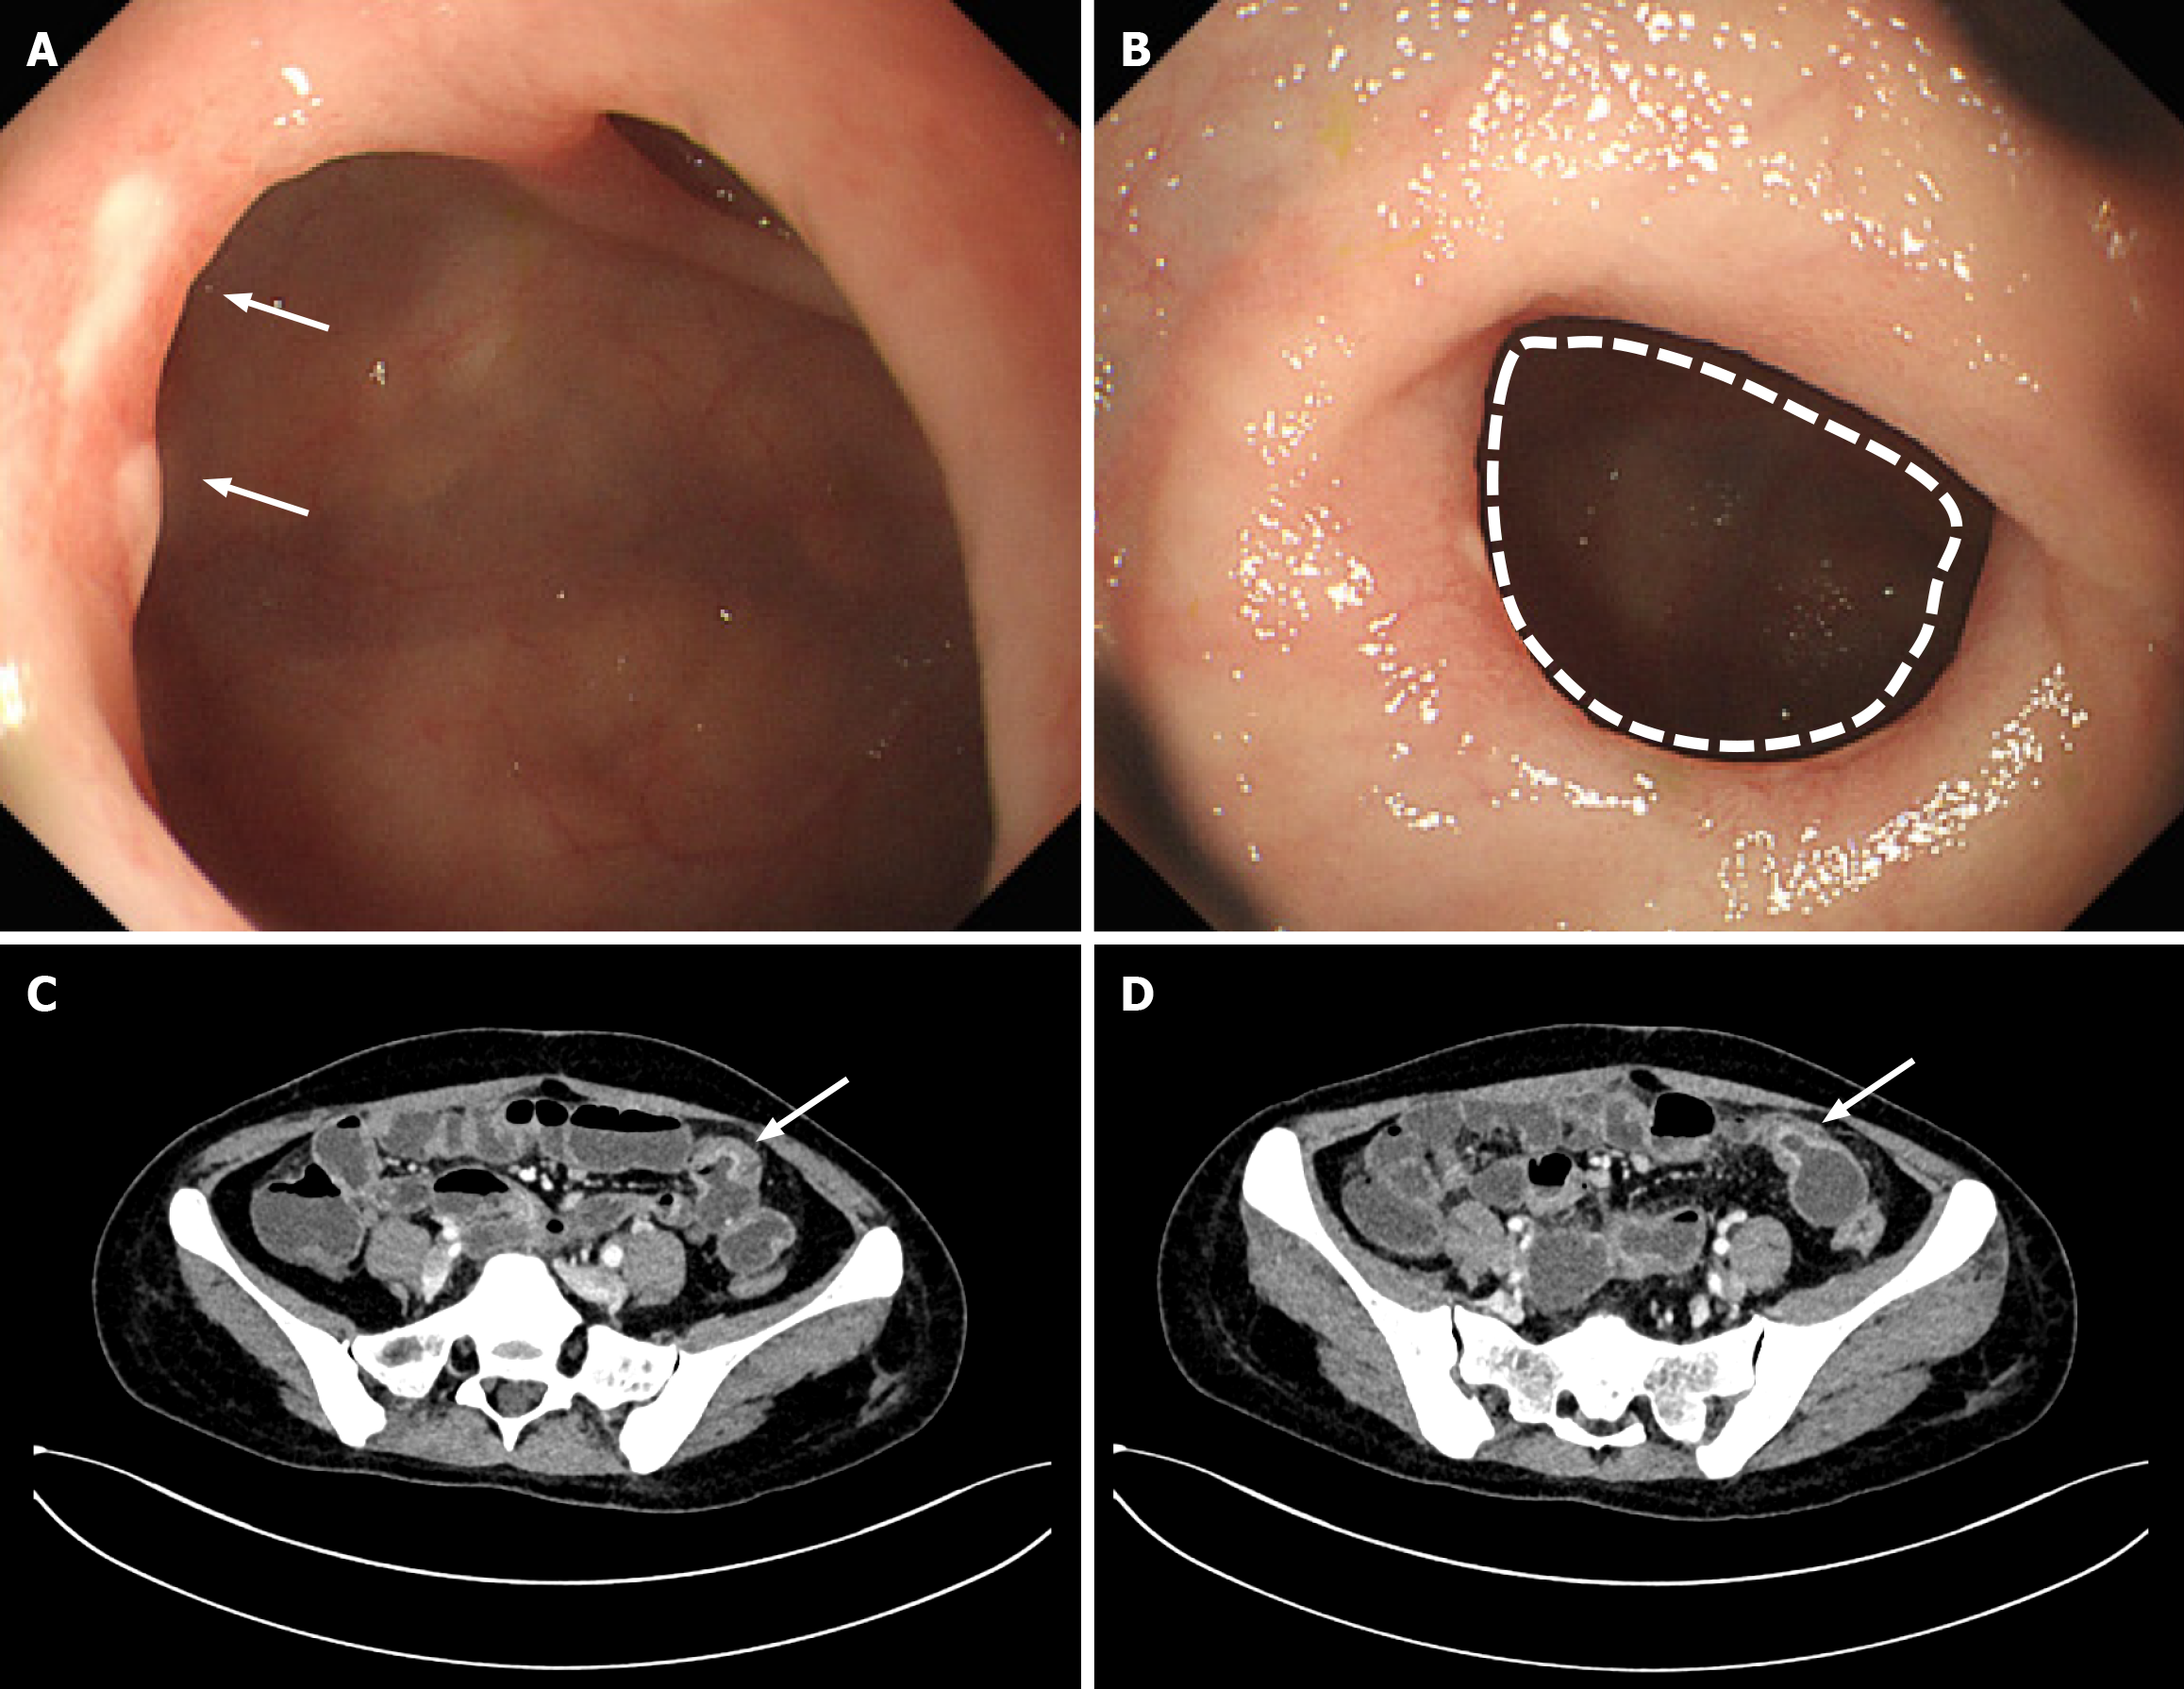

Gastroduodenoscopy showed the esophagus, stomach, and duodenum mucosa appeared normal. Colonoscopy showed lymphoid follicular hyperplasia in the terminal ileum, with no abnormalities in the rectal mucosa. The pathology indicated chronic inflammation in the ileum. Considering the patency capsule had been blocked in the small bowel in the reported CEAS patient[11], we preferred gastrointestinal ultrasound and computed tomography enterography (Figure 1), which showed multiple segments of the small intestine in the lower left abdomen and pelvic area were thickened and enhanced, with ulcer formation. The enteroscopy (Figure 1) revealed multiple circular and tape-like shallow ulcers in the ileum (about 150-200 cm from the ileocecal valve), and the enteroscopy could not pass through due to intestinal stenosis (about 200 cm from the ileocecal valve). The pathology indicated chronic inflammation in the ileum, with scattered lymphocytes, plasma cells, and eosinophils.

Figure 1

Figure 1 Endoscopic features and radiographic findings of patients diagnosed with chronic enteropathy associated with the solute carrier organic anion transporter family member 2A1 gene. A and B: Enteroscopy revealed multiple circular, tape-like, shallow ulcers and intestinal stenosis in the ileum; C and D: Computed tomography enterography showed multiple segments of the small intestine in the lower left abdomen, and the pelvic area was thickened and enhanced, with ulcer formation. Arrows indicate ulcers; dashed lines indicate intestinal stenosis.